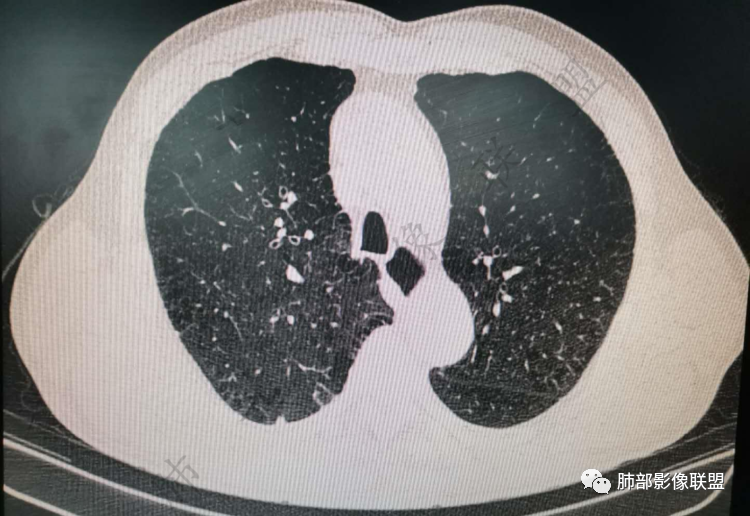

右肺上类圆形叶结节,周边见细软毛刺,增强后呈环形明显强化,内部坏死,邻近胸膜光滑,结合病史2个月明显增大,考虑炎性可能性大。

老年男性,炎性指标略高,肺气肿背景。右肺上叶胸膜下结节,部分边缘平直,部分稍模糊,软长毛刺,血管增粗,病灶中心密度减低,邻近脂肪间隙清晰。考虑炎性肉芽肿或慢性炎症,鉴别鳞癌。

老年男性,炎性指标略高,肺气肿背景。右肺上叶胸膜下结节,部分边缘平直,部分稍膨隆,供血血管增粗,增强扫描病灶中心密度减低,呈环形强化,邻近脂肪间隙清晰。考虑炎性肉芽肿或慢性炎症,鉴别鳞癌。

右肺上叶前段胸膜下结节,边缘分叶毛刺,血管集束,支气管截断,纵膈胸膜牵拉,内乳动脉增粗,密度不均,中央可见坏死,两个月短期随访结节有增大,考虑恶性,腺癌。鉴别结核。

肺气肿背景,右肺上叶纵隔旁胸膜下结节,有血管集束,支气管堵塞,内乳动脉增粗,增强不均匀强化,内可见低密度区。考虑为恶性可能性大

老年男性,肺气肿背景,右肺上叶胸膜下弧立实性不规则结节,密度不均,其内低密度坏死影,支气管似有截断,血管集束,2月复查明显增大,考虑恶性,鳞癌可能大,鉴别炎性肉芽肿

老年男性,炎性指标略高。影像表现右肺上叶胸膜下结节,膨胀性生长部分边缘平直,边界清晰,病灶可见血管集束征,近段支气管阻断?增强扫描病灶中心密度减低,低密度区边界模糊,外围环形强化。老年性,不能排除恶性病变,周围性鳞癌,其次才考虑炎性肉芽肿或慢性炎症

老年男性,肺气肿背景,右肺上叶前段胸膜下结节,部分边缘毛糙,血管集束增粗,支气管似有截断,胸膜牵拉,结节密度不均,两个月随访结节有增大,考虑恶性,肺癌可能;另右肺上叶后段肋胸膜区小片状类结节影,考虑炎性可能。

右肺上叶前段胸膜下结节,近段支气管截断,血管伸入结节内,密度不均,同侧临近内乳动脉增粗,不均匀强化,肺气肿背景,两月明显增大,考虑低分化鳞癌,隐球菌代排

老年男性,白细胞计数及CRP稍高,右肺上叶结节,两个月来有增大,部分边缘可见边界模糊的GGO,局部边缘平直、凹陷,临近胸膜增厚,内见坏死,坏死区边界未见明显壁结节,壁较厚而且均匀强化,支气管似乎有扩张然后截断,近端血管增粗明显。考虑炎性病变,脓肿?有结核病人密切接触史,注意是否为结核。有点难以理解的是为什么右侧内乳动脉增粗明显。

老年男性,无症状,炎性指标增高。肺气肿背景,右肺上叶前段结节,边缘部分平直部分澎隆,血管集束,支气管至病变边缘似截断,近端扩张。增强环形强化,中心坏死。两月内病灶增长太快,考虑炎性肉芽肿,慢性脓肿?结核?癌待排。

肺气肿背景

支气管变形、壁增厚,提示慢性支气管炎症

边缘平直

宽基底与胸膜相连,附近胸膜增厚,糊墙

内部有低强化区,边界尚清

还是支持炎性放前面,恶性待排